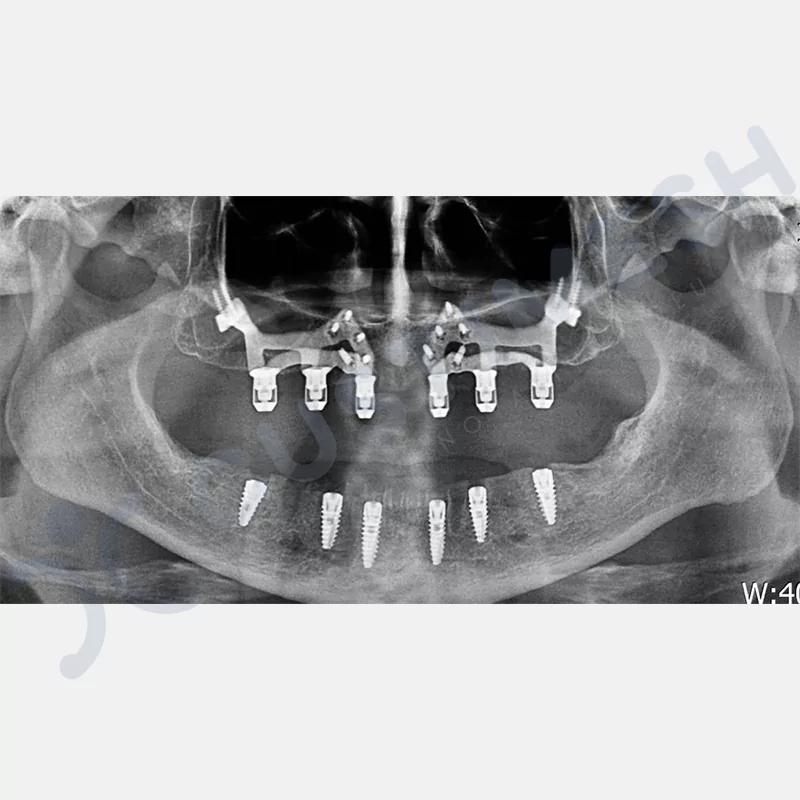

Modern diş hekimliğinde, çene gelişimini tamamlamamış veya ciddi kemik kaybı yaşayan hastalar için kişiye özel titanyum implantlar ile çözüm bulunmaktadır. CAD/CAM teknolojisi ve lazer sinterleme yöntemiyle üretilen bu implantlar, hastanın bireysel anatomik yapısına tam uyum sağlayarak geleneksel implantların uygulanamadığı vakalarda mükemmel bir alternatif oluşturmaktadır. Özellikle ileri derecede kemik kaybı olan hastalar için geliştirilen subperiosteal implantlar, periostun altına yerleştirilerek minimal invaziv bir yaklaşım sunarken, bilgisayarlı tomografi verileri ve sonlu eleman analizleriyle optimize edilmiş tasarımları sayesinde hem estetik hem de fonksiyonel sonuçlar garanti etmektedir. Bu yenilikçi teknoloji, tek seansta implant ve protez uygulamasına imkan vererek hastaların aynı gün doğal gülüşlerine kavuşmalarını sağlarken, kemik greftleme gibi ek işlem ihtiyacını ortadan kaldırarak cerrahi süreci büyük ölçüde kolaylaştırmaktadır. Kişiye özel tasarımı ve üstün biyouyumluluğu sayesinde, daha önce tedavisi mümkün görülmeyen kompleks vakalarda bile başarılı sonuçlar sunan bu implantlar, modern diş hekimliğinde yeni bir çağ açarak hastaların yaşam kalitesini artırmayı hedeflemektedir.

VAKA 4